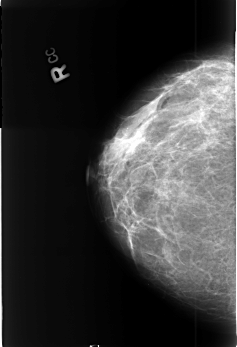

B_3376_1.RIGHT_MLO

RIGHT_CC LINES 4504 PIXELS_PER_LINE 3080 BITS_PER_PIXEL 12 RESOLUTION 50 NON_OVERLAY

RIGHT_MLO LINES 4488 PIXELS_PER_LINE 3032 BITS_PER_PIXEL 12 RESOLUTION 50 NON_OVERLAY